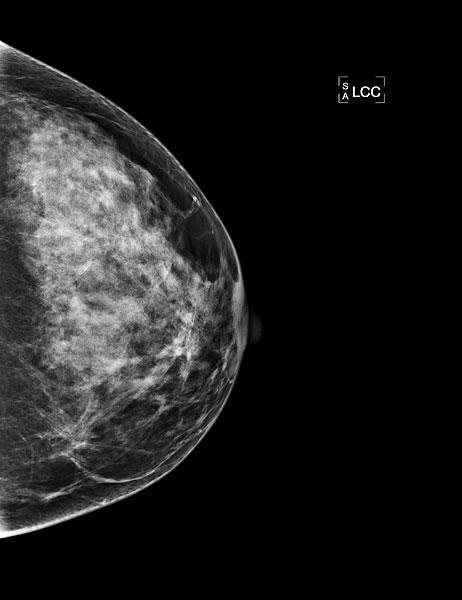

Die Basis der Brustdiagnostik ist die Mammographie, die Methode zur Früherkennung von Brustkrebs. Die Mammographie wird mit einem speziellen Röntgen-Gerät durchgeführt. Die Brust wird zwischen zwei Plexiglasplatten gelegt und leicht zusammengepresst, um eine möglichst dünne Schicht mit wenig Überlagerung zu erhalten. Die Aufnahme dauert nur einen Sekundenbruchteil und ist nicht spürbar. Jede Brust wird in zwei verschiedenen Ebenen geröntgt.